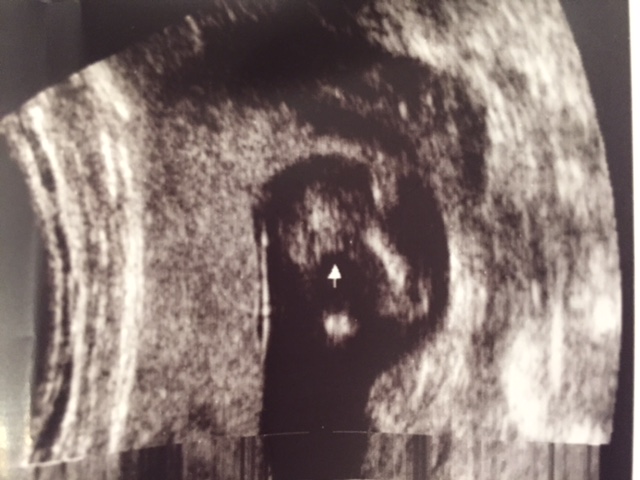

Potty shot at 13 weeks scan. Please help!!